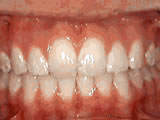

Missing lateral incisors

missing incisors before

Before

missing incisors after

After

This patient's lateral incisors were congenitally missing. She had braces for 20 months to move the teeth into their correct positions, then the missing teeth were replaced with bonded "Maryland" bridges.